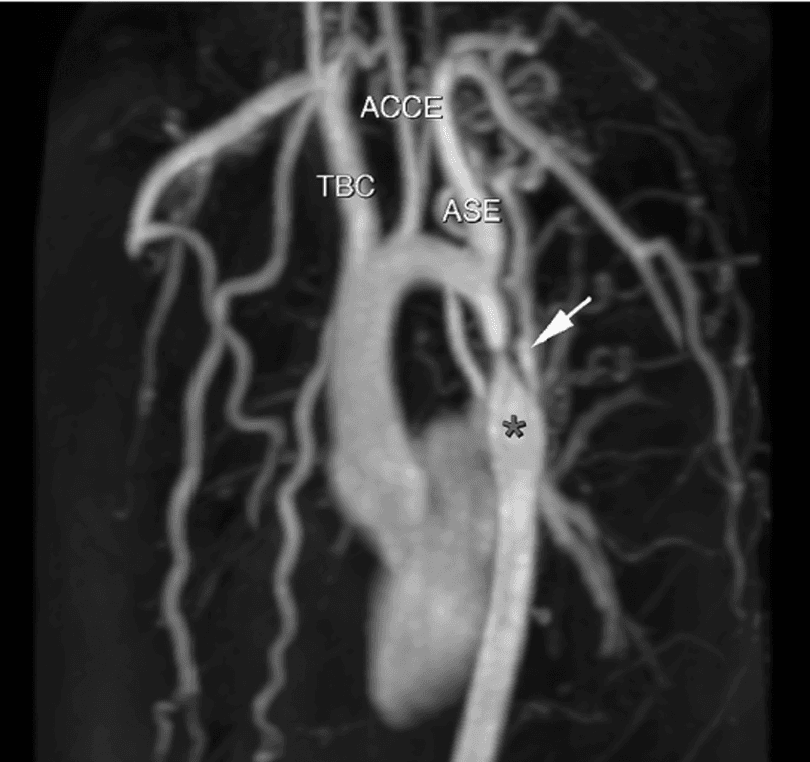

Consiste em estreitamento do lúmen da aorta situado na maioria das vezes ( 96% ) na região localizada entre a origem da artéria subclávia esquerda e a região do canal arterial ( istmo da aorta ).